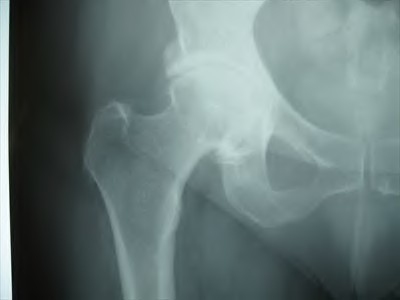

A 45-year-old female with developmental dysplasia of the hip (DDH) presents for THA. Preoperative radiographs show the femoral head is subluxated, with 80% proximal migration relative to the height of the normal true acetabulum. Based on the Crowe classification, what type of dysplasia does she have?

Explanation